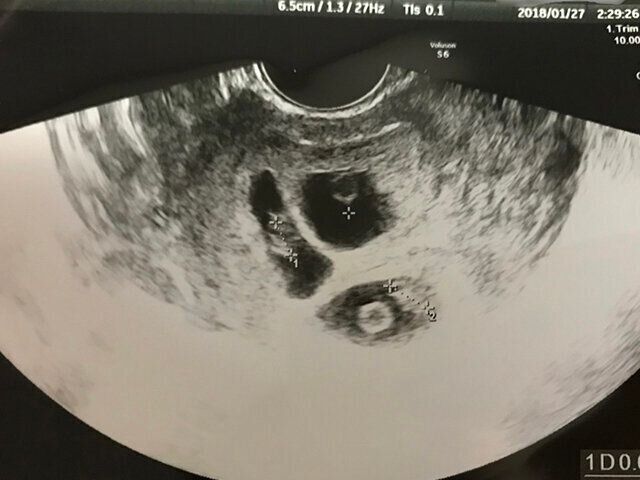

2回目の健診は、長女と夫を連れて家族3人で健診に行きました。ところが、エコーを開始したところ、あきらかにおなかの中で3つの心臓が動いていてびっくり。先生にも『3人いますね!』と言われ、まさかの三卵性の3つ子だということが判明しました!1回目の健診ではバニッシングツインを心配していましたが、1人消えるどころか1人増えていたのでうれしい気持ちでいっぱいでした。